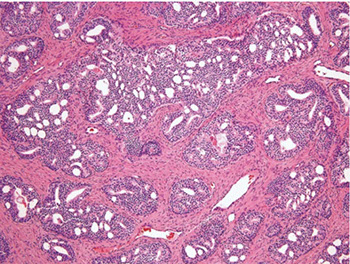

Prostatic Duct AC

Ductal Adenocarcinoma

Hard to diff HG-PIN and ductal AC

- ductal ACs are agressive, advanced stage, and assoc c a poor px

- critical to diff from PIN

- ductal AC usually centrally located in periurethral region and sampled on TURP

-- PIN uncommon in periurethral region and infreq seen on TURP

- ductal AC usually has true papillary fronds c well-formed fibrovascular core, whereas HG-PIN more freq reveals micropapillary fronds c tall columns of epithelium w/o fibrovascular stalks

- ductal AC freq has comedonecrosis, which can be extensive

-- HG-PIN lacks comedonecrosis

- ductal AC can consist of large or back-to-back glands, whereas glands c PIN are of the size and distribution of b9 glands

- use of basal cell markers in the DDx can be problematic as both HG-PIN and ductal AC can have a patchy basal cell layer, however, the lack of a basal cell layer in numerous glands rules out PIN

Although the MC forms of ductal AC mimic cribriform and micropapillary HG-PIN, ductal AC can be composed of simple glands lined by stratified columnar epithelium c cytologic and architectural features of flat and tufting HG-PIN

- these PIN-like ductal cancers are distinguished from HG-PIN either bc the atypical glands are too crowded to represent HG-PIN or there are too many atypical glands that are negative for basal cell markers to be consistent with HG-PIN

- additional differences are in the PIN-like ductal AC, many of the glands are lined by flat epithelium (an uncommon pattern in HG-PIN) and the glands are often cystically dilated

Px: up to 1/2 metastatic at dx

Ductal AC